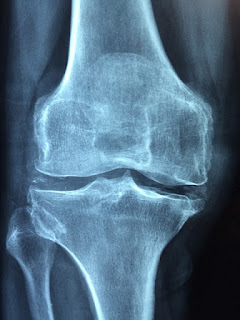

PRP or Platelet Rich Plasma treatment includes infusing platelet advanced plasma extricated from a patient's blood into their own body's tissues. The outcome is a speedier mitigation or decrease in agony and recuperation rate from a physical issue, including those from a surgery. Platelet-rich plasma is determined when blood is spun in a rotator. The fluid constituent of the blood, i.e., the plasma isolates from the strong segments, for example, red and white platelets and platelets. The last are expelled while the previous are recombined with the plasma. We also provide IV therapy in Los Angeles along with pain management. Rewarding Chronic and Unresponsive Issues One of the primary reasons why PRP treatment has picked up prominence today is a result of its viability in rewarding lethargic issues. You may have an injury that hasn't recuperated the manner in which it ought to or know somebody whose wounds aren't mending as quick they typically do. This is the place t...